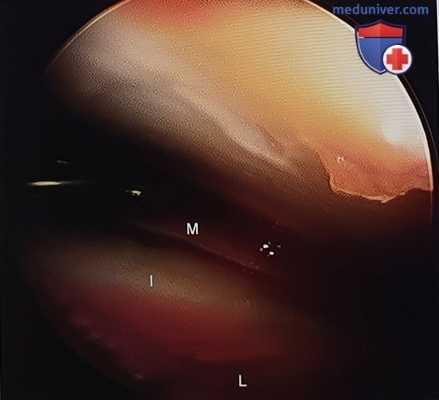

Рисунок 10. Фрагмент задней фасетки после анатомичной репозиции. I — промежуточный фрагмент, L — латеральный фрагмент, М — медиальный фрагмент.

Нюансы 3 этапа операции:

• Удаление клетчатки из пазухи предплюсны и дистракция подтаранного сустава с помощью пластинчатого дистрактора обычно позволяет значительно улучшить визуализацию

• Если визуализация все еще недостаточна, для контроля качества репозиции можно воспользоваться тонким элеватором, которым проводят по суставной поверхности

• Репозиция задней фасетки начинается с наиболее медиального фрагмента, который репонируется относительно опоры таранной кости

• Для репозиции мелких фрагментов можно использовать стоматологический остроконечный зонд

• Задняя суставная фасетка пяточной кости имеет выпуклую форму, поэтому после репозиции латеральных фрагментов визуальный контроль репозиции ограничивается

• Использование небольшого артроско-па является быстрым и надежным методом контроля качества репозиции (рис. 10)